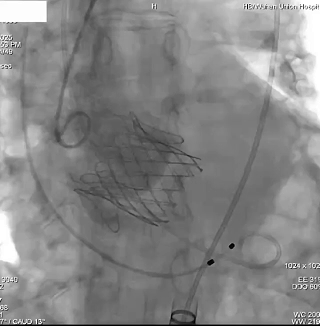

瓣膜释放

瓣膜释放后造影检查瓣膜位置,功能、形态良好,未见明显反流及瓣周漏